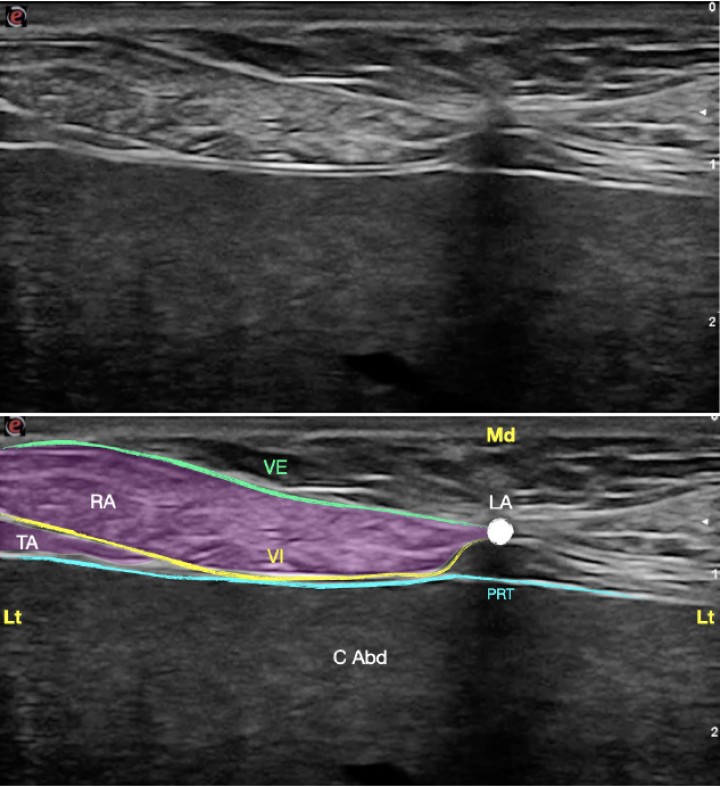

<p>Imagen ecográfica de la vaina del recto del abdomen. Músculo recto del abdomen (RA), músculo transverso abdominal (TA), vaina externa (VE), vaina interna (VI), línea alba (LA), peritoneo (PRT), cavidad abdominal (C Abd). Lt: Lateral, Md: Medial.</p>

Figura 12

Imagen ecográfica de la vaina del recto del abdomen. Músculo recto del abdomen (RA), músculo transverso abdominal (TA), vaina externa (VE), vaina interna (VI), línea alba (LA), peritoneo (PRT), cavidad abdominal (C Abd). Lt: Lateral, Md: Medial.

<p>(<strong>A</strong>) Posición del transductor y la aguja para el abordaje en plano de la vaina del recto del abdomen. (<strong>B</strong>) Imagen esquemática de las estructuras anatómicas y la aguja. Músculo recto del abdomen (RA), músculo transverso abdominal (TA), vaina externa (VE), vaina interna (VI), línea alba (LA), peritoneo (PRT), cavidad abdominal (C Abd). Lt: Lateral, Vt: Ventral.</p>

Figura 16

(A) Posición del transductor y la aguja para el abordaje en plano de la vaina del recto del abdomen. (B) Imagen esquemática de las estructuras anatómicas y la aguja. Músculo recto del abdomen (RA), músculo transverso abdominal (TA), vaina externa (VE), vaina interna (VI), línea alba (LA), peritoneo (PRT), cavidad abdominal (C Abd). Lt: Lateral, Vt: Ventral.